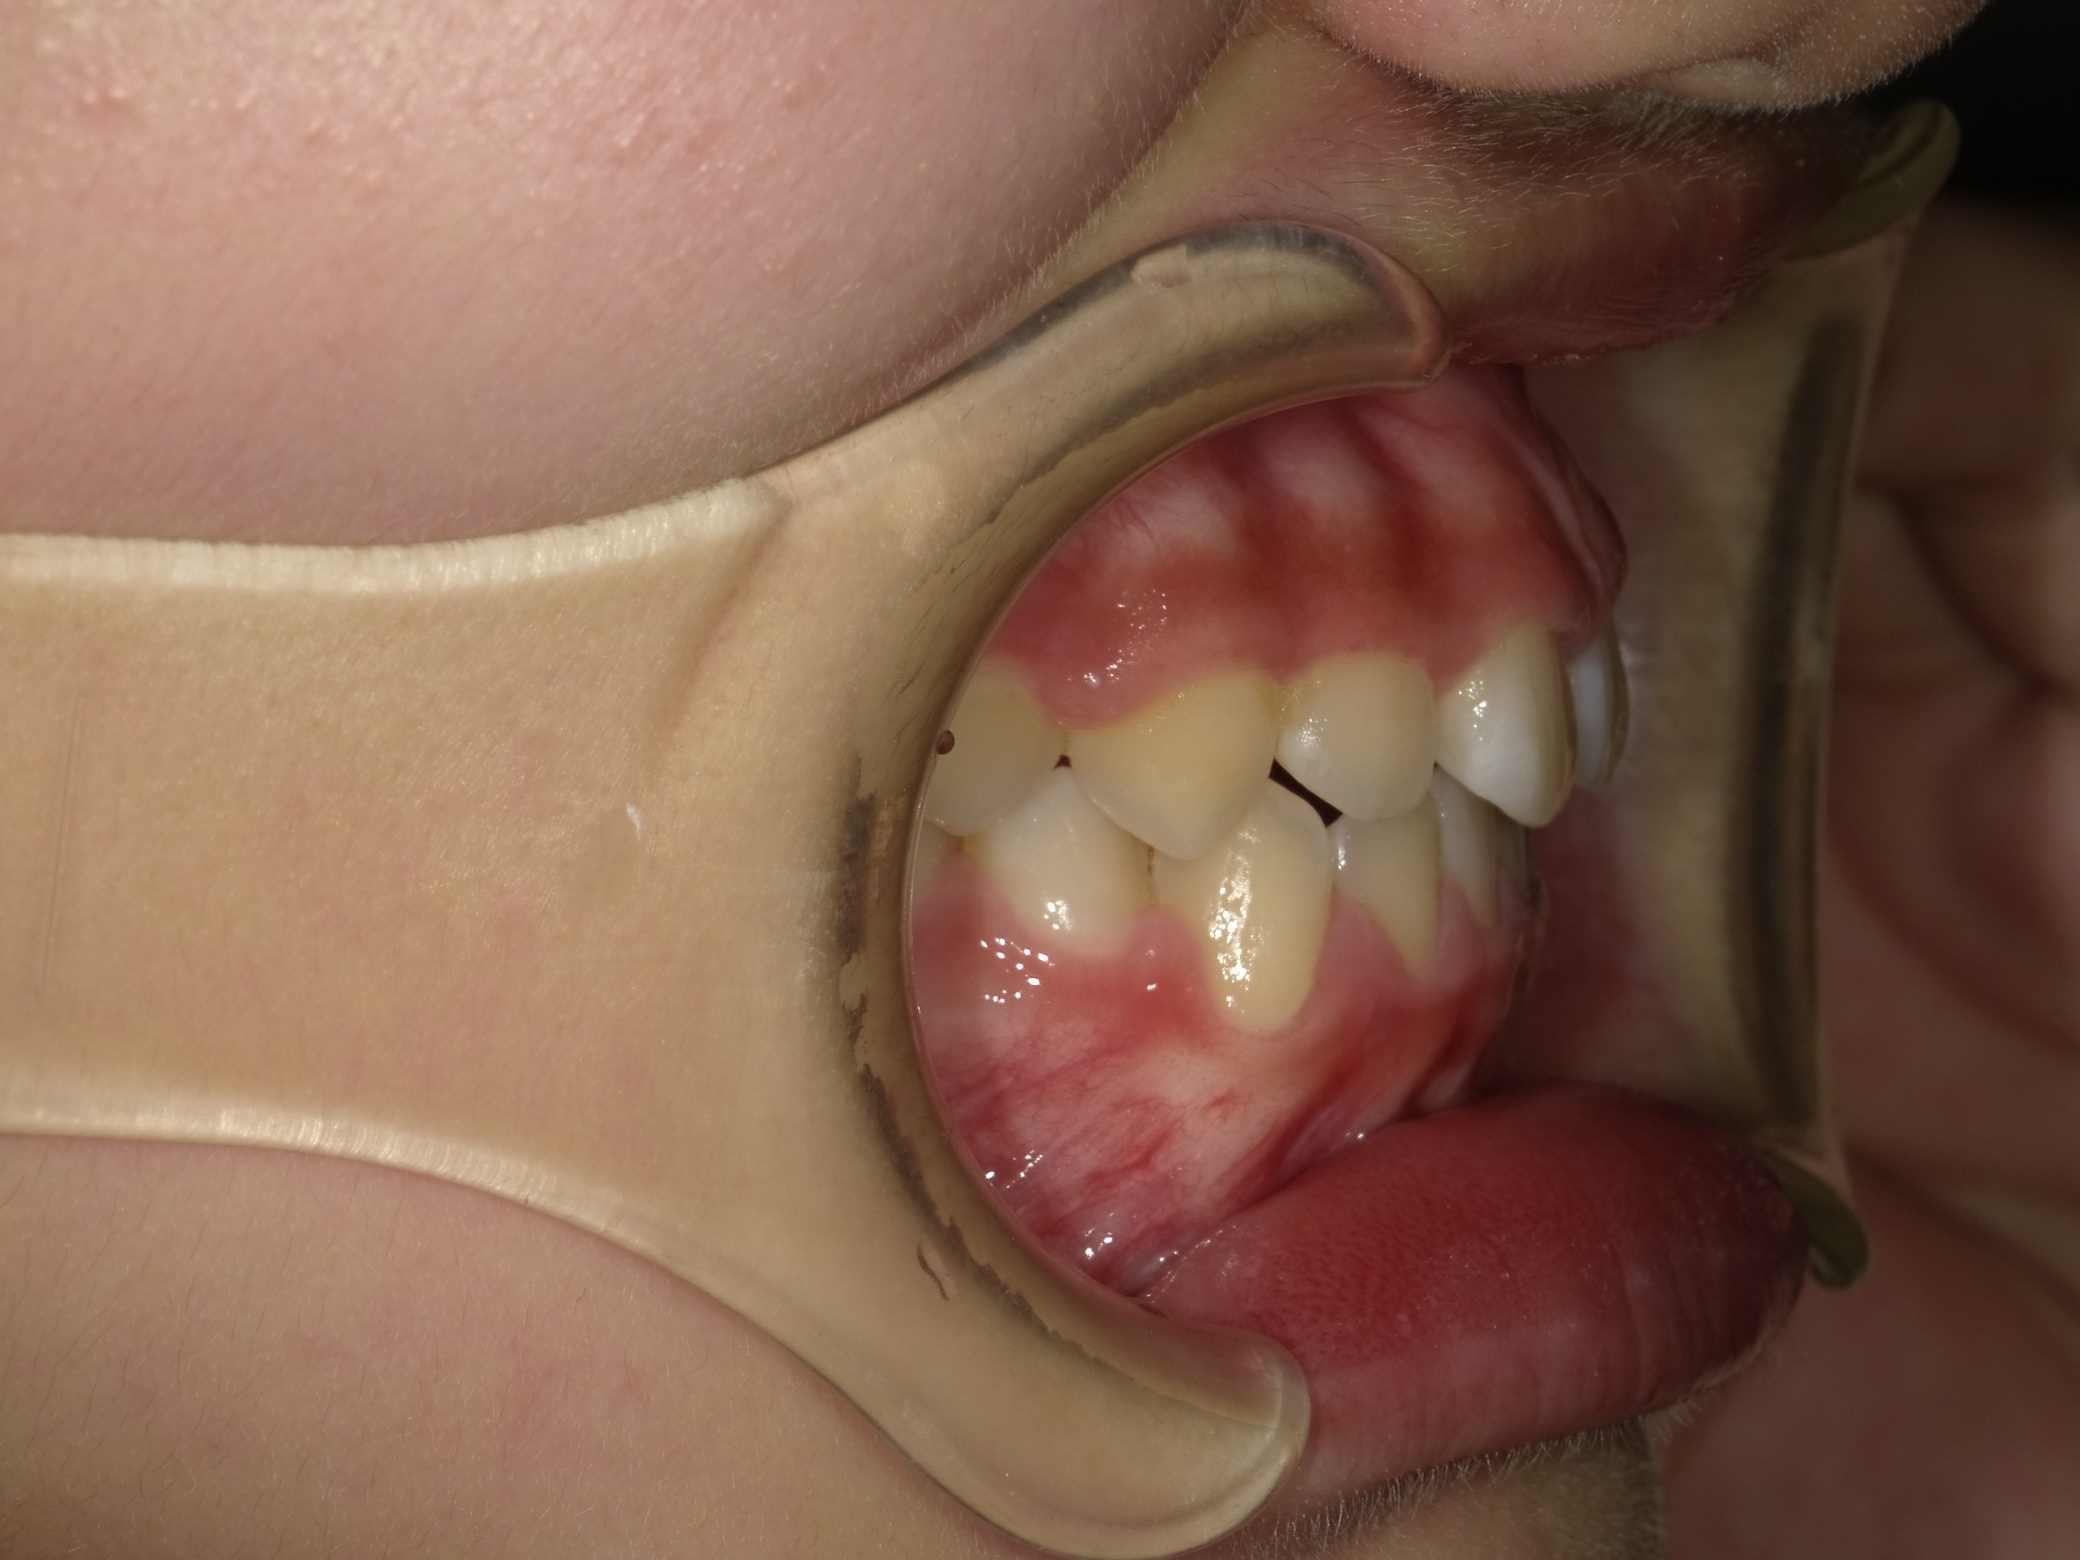

右横